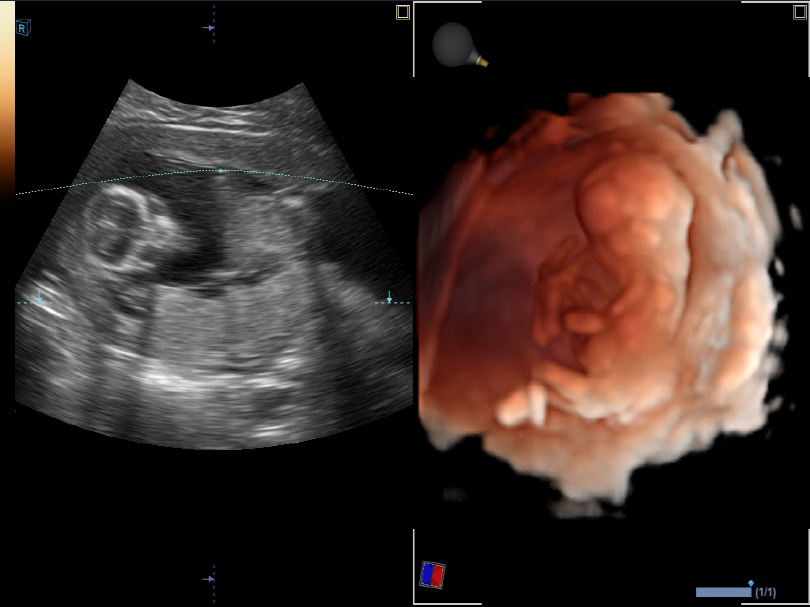

Satisfaction with Image Quality

High-Resolution TransducersTransducers powered by PowerView™